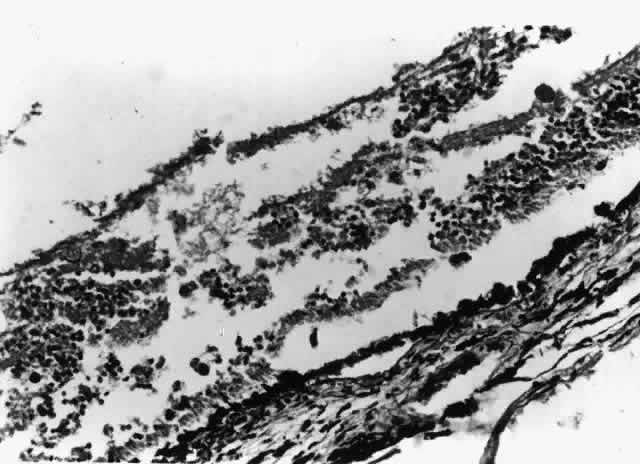

Nontuberculous mycobacterial infections can also produce choroidal granulomata, in which acid-fast bacilli can be found in histiocytes (Fig. 6). Mycobacterium avium complex is the most common cause. Infections have been reported most commonly as incidental findings at autopsy,9,17 although round, yellow-white lesions resembling choroidal pneumocystosis on fundus examination have been confirmed to be nontuberculous mycobacterial granulomata.31